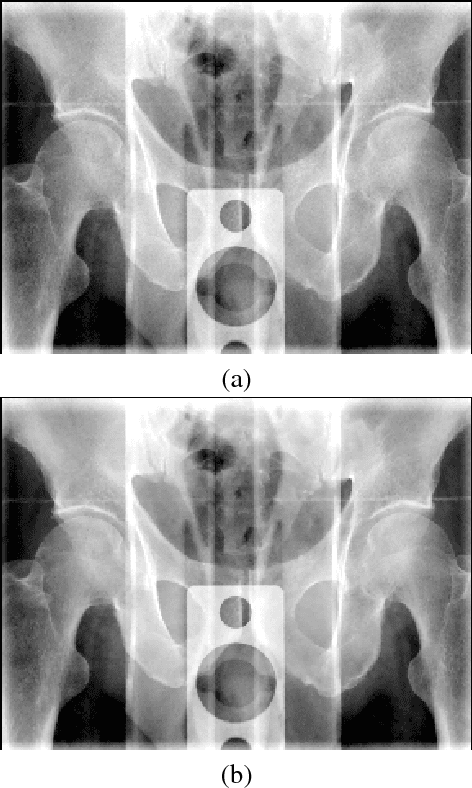

Abstract:High-frequency noise is present in several modalities of medical images. It originates from the acquisition process and may be related to the scanner configurations, the scanned body, or to other external factors. This way, prospective filters are an important tool to improve the image quality. In this paper, we propose a non-local weighted operational anisotropic diffusion filter and evaluate its effect on magnetic resonance images and on kV/CBCT radiotherapy images. We also provide a detailed analysis of non-local parameter settings. Results show that the new filter enhances previous local implementations and has potential application in radiotherapy treatments.